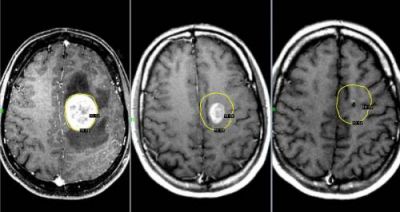

Опухоль мозга

Данное новообразование появляется в тканях мозга и может быть как злокачественным, так и доброкачественным. Последнее можно вылечить без хирургического вмешательства. Злокачественная опухоль растет очень быстро и дает метастазы. Поэтому лечению заболевание поддается с трудом, особенно на поздних стадиях.

При данном заболевании боль ощущается постоянно, а во время движения только усиливается. Самые сильные боли бывают в утреннее и ночное время вследствие накопления избыточной жидкости в тканях. Характер боли — давящий, пульсирующий.

Опухоли мозга

Злокачественные опухоли характеризуются быстрым прорастанием в другие ткани с их последующей трансформацией. При этом метастазы могут наблюдаться сразу в нескольких участках мозга.

Такие опухоли плохо лечатся, а на поздних стадиях их развития спасти человека практически невозможно.

Клиническая картина

Характер болевых ощущений — постоянный, по мере развития заболевания продолжительность приступов увеличивается. Когда человек двигается, болевые ощущения усиливаются. Сначала они локализуются в области опухоли, потом, по мере увеличения внутричерепного давления, переходят в лобную и затылочную часть. Наиболее сильный дискомфорт наблюдается в ночное и утреннее время из-за скопления жидкости. Вены не справляются с оттоком крови, поэтому к болям прибавляются отёчность и застои. Боли давящие, распирающие, пульсирующие.

К головным болям затем добавляется рвота. При физической нагрузке или кашле болевые ощущения усиливаются, появляется двоение в глазах, временами исчезает зрение. Голова кружится, у пациента нарушается координация движений. Могут неметь конечности, ослабляется тонус мышц.

Диагностирование

Для диагностики используется МРТ мозга, ПЭТ, КТ мозга, ангиография и другие методы.